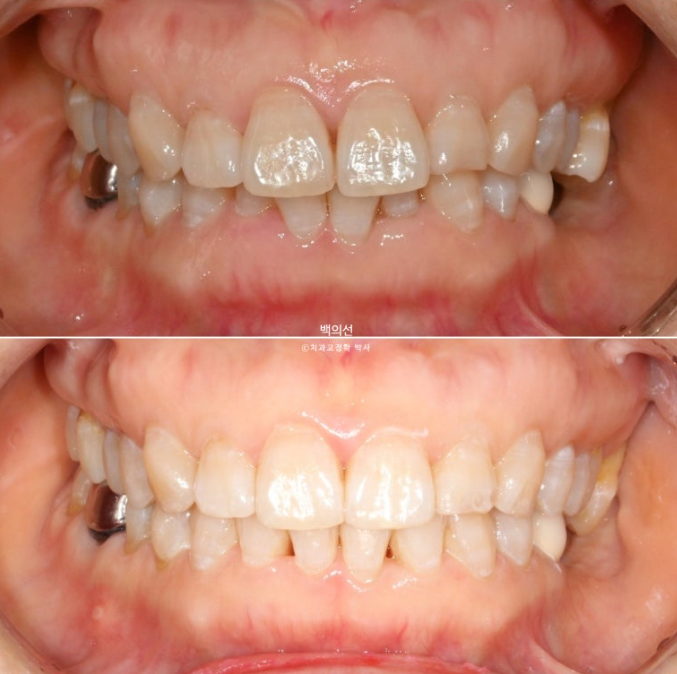

25년 4월부터 7월까지, 4개월간 14개 추가장치를 모두 낀 후 모습입니다.

25.07

교합이 좋지 않으면 치료를 마무리 짓지 않습니다.

유지장치까지 깔끔하게 들어간 모습입니다.

이제 전후 비교 보겠습니다.

총 치료기간은 10개월 입니다.

과개교합과 중심선의 개선.

내려오고 튀어나와 있던 가운데 앞니는 뒤로 이동하며 돌출감이 줄었습니다